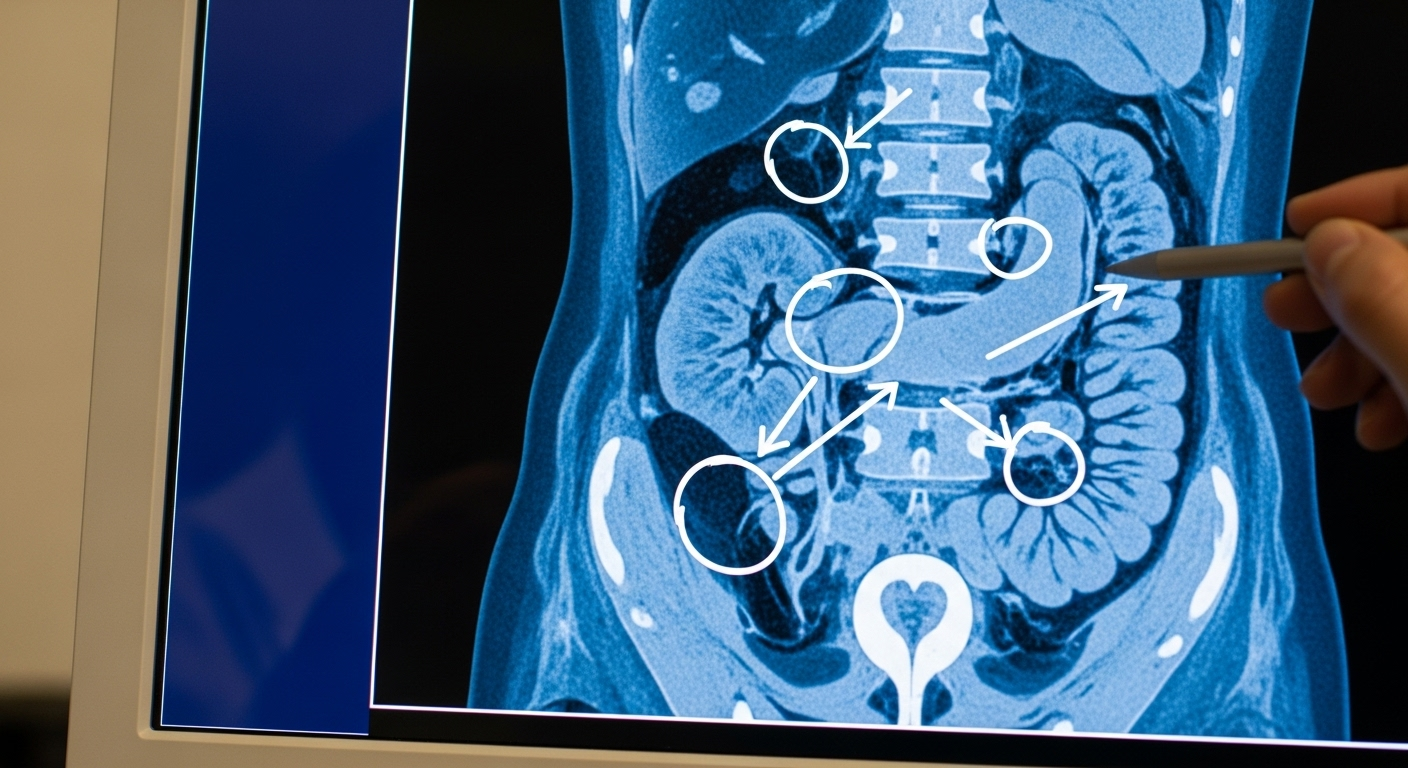

Le scanner va encore plus loin. Il dresse un bilan alarmant : foie hypertrophié, voies biliaires épaissies, ganglions enflés, et même un caillot de sang dans la veine du rein droit. Mais l’élément le plus étrange, c’est cette découverte d’un « pont de tissus mous » reliant son intestin grêle à son rein droit. Une anomalie anatomique qui n’a aucun sens.